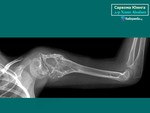

Установить, что у пациента саркома Юинга и ПНЭО смогут специалисты после того, как будут сделан рентгенологическое исследование места поражения.

Для установления окончательного диагноза пациенту проводят компьютерную томографию или магнитно-резонансную томография костей и мягких тканей. Кроме того, выполняется ряд исследований для точной оценки характера новообразования.

Данные исследований КТ и МРТ позволят специалистам точно определить размеры новообразования, степень распространенности и поражение близлежащих тканей.

И первым исследованием, позволяющим заподозрить саркому Юинга, становится рентгенография пораженной кости. Для данного патологического процесса характерно сочетание реактивного и деструктивного процессов костеобразования. Контуры кортикального слоя нечеткие, определяется расслоение и разволокнение кортикальной пластинки.

При вовлечении в процесс надкостницы на рентгенограмме выявляются мелкие пластинчатые или игольчатые образования. Кроме того, на снимках видна область изменения мягких тканей, по своему размеру превышающая первичную костную опухоль. При этом мягкотканный опухолевый компонент отличается однородностью, хрящевые включение, очаги обызвествления или патологического костеобразования отсутствуют.

При выявлении типичных рентгенологических признаков саркомы Юинга больного направляют в отделение онкологии, где проводится расширенное обследование для оценки состояния первичного очага и выявления метастазов. В ходе такого обследования выполняется компьютерная томография или магнитно-резонансная томография костей и мягких тканей, пораженных злокачественным процессом.

Данные исследования позволяют точно определить размер новообразования, степень его распространения по костно-мозговому каналу, связь с сосудисто-нервным пучком и окружающими тканями.